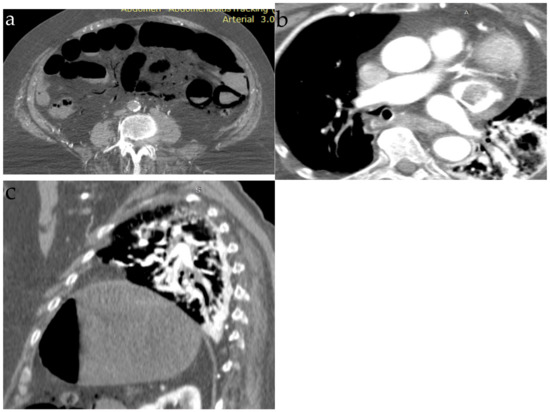

3. Fat Embolism

3.5. Imaging Findings

| Computer tomography | Small amount of air in the main pulmonary artery, on the right heart or systemic veins; in severe cases, pulmonary hypertension and right heart strain are found | Ground-glass opacities, interlobar septal thickening with the pattern of “crazy paving” | Diffuse bilateral ground-glass opacities | Bilateral lung nodules, located mainly in the peripheral lung areas and in the lower lobes, mediastinal or hilar lymphadenopathy, a dilated pulmonary branch (mycotic aneurysm) and feeding vessel sign | The classic finding (affected centrilobular arteries) is an image of “tree-in-bud”; in cases where the main arteries are affected, the findings are filling defects that resemble acute or chronic pulmonary emboli |